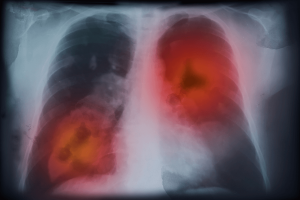

The increasing effects of aging and global population growth, along with improved cancer survivorship due to early detection and treatment, have made cancer a significant public health challenge. Active cancer (with ongoing treatment), venous thromboembolism (VTE), including pulmonary embolism and deep venous thrombosis, together rank as the second leading cause of death after cancer itself.

Low-dose aspirin has both antithrombotic and anticancer properties and has been proposed for use in certain cancer patients to help prevent the development of VTE. The risk of VTE can be decreased by low-dose aspirin without significantly increasing the risk of bleeding. However, it remains unclear whether this drug can reduce the recurrence of VTE in patients with cancer. The aim of the proposed research was to analyse whether the addition of aspirin to standard anticoagulation therapy leads to improved short-term outcomes in patients with cancer-associated VTE.